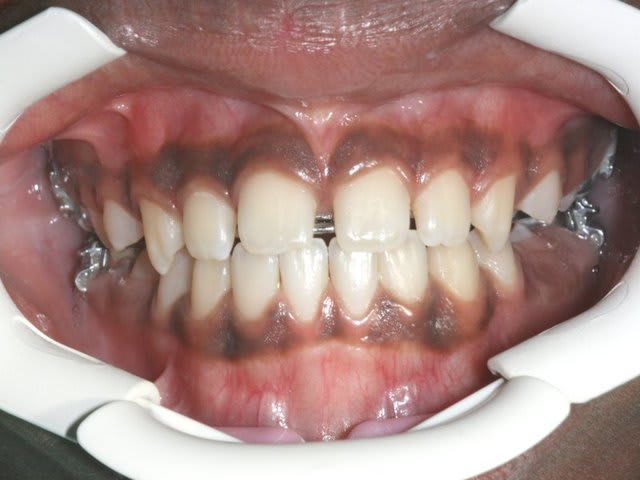

Dam. A.

Age :8 ans

Sexe M.

CL. III.

J’ai demandé à voir les parents, voici les dents du père !!!